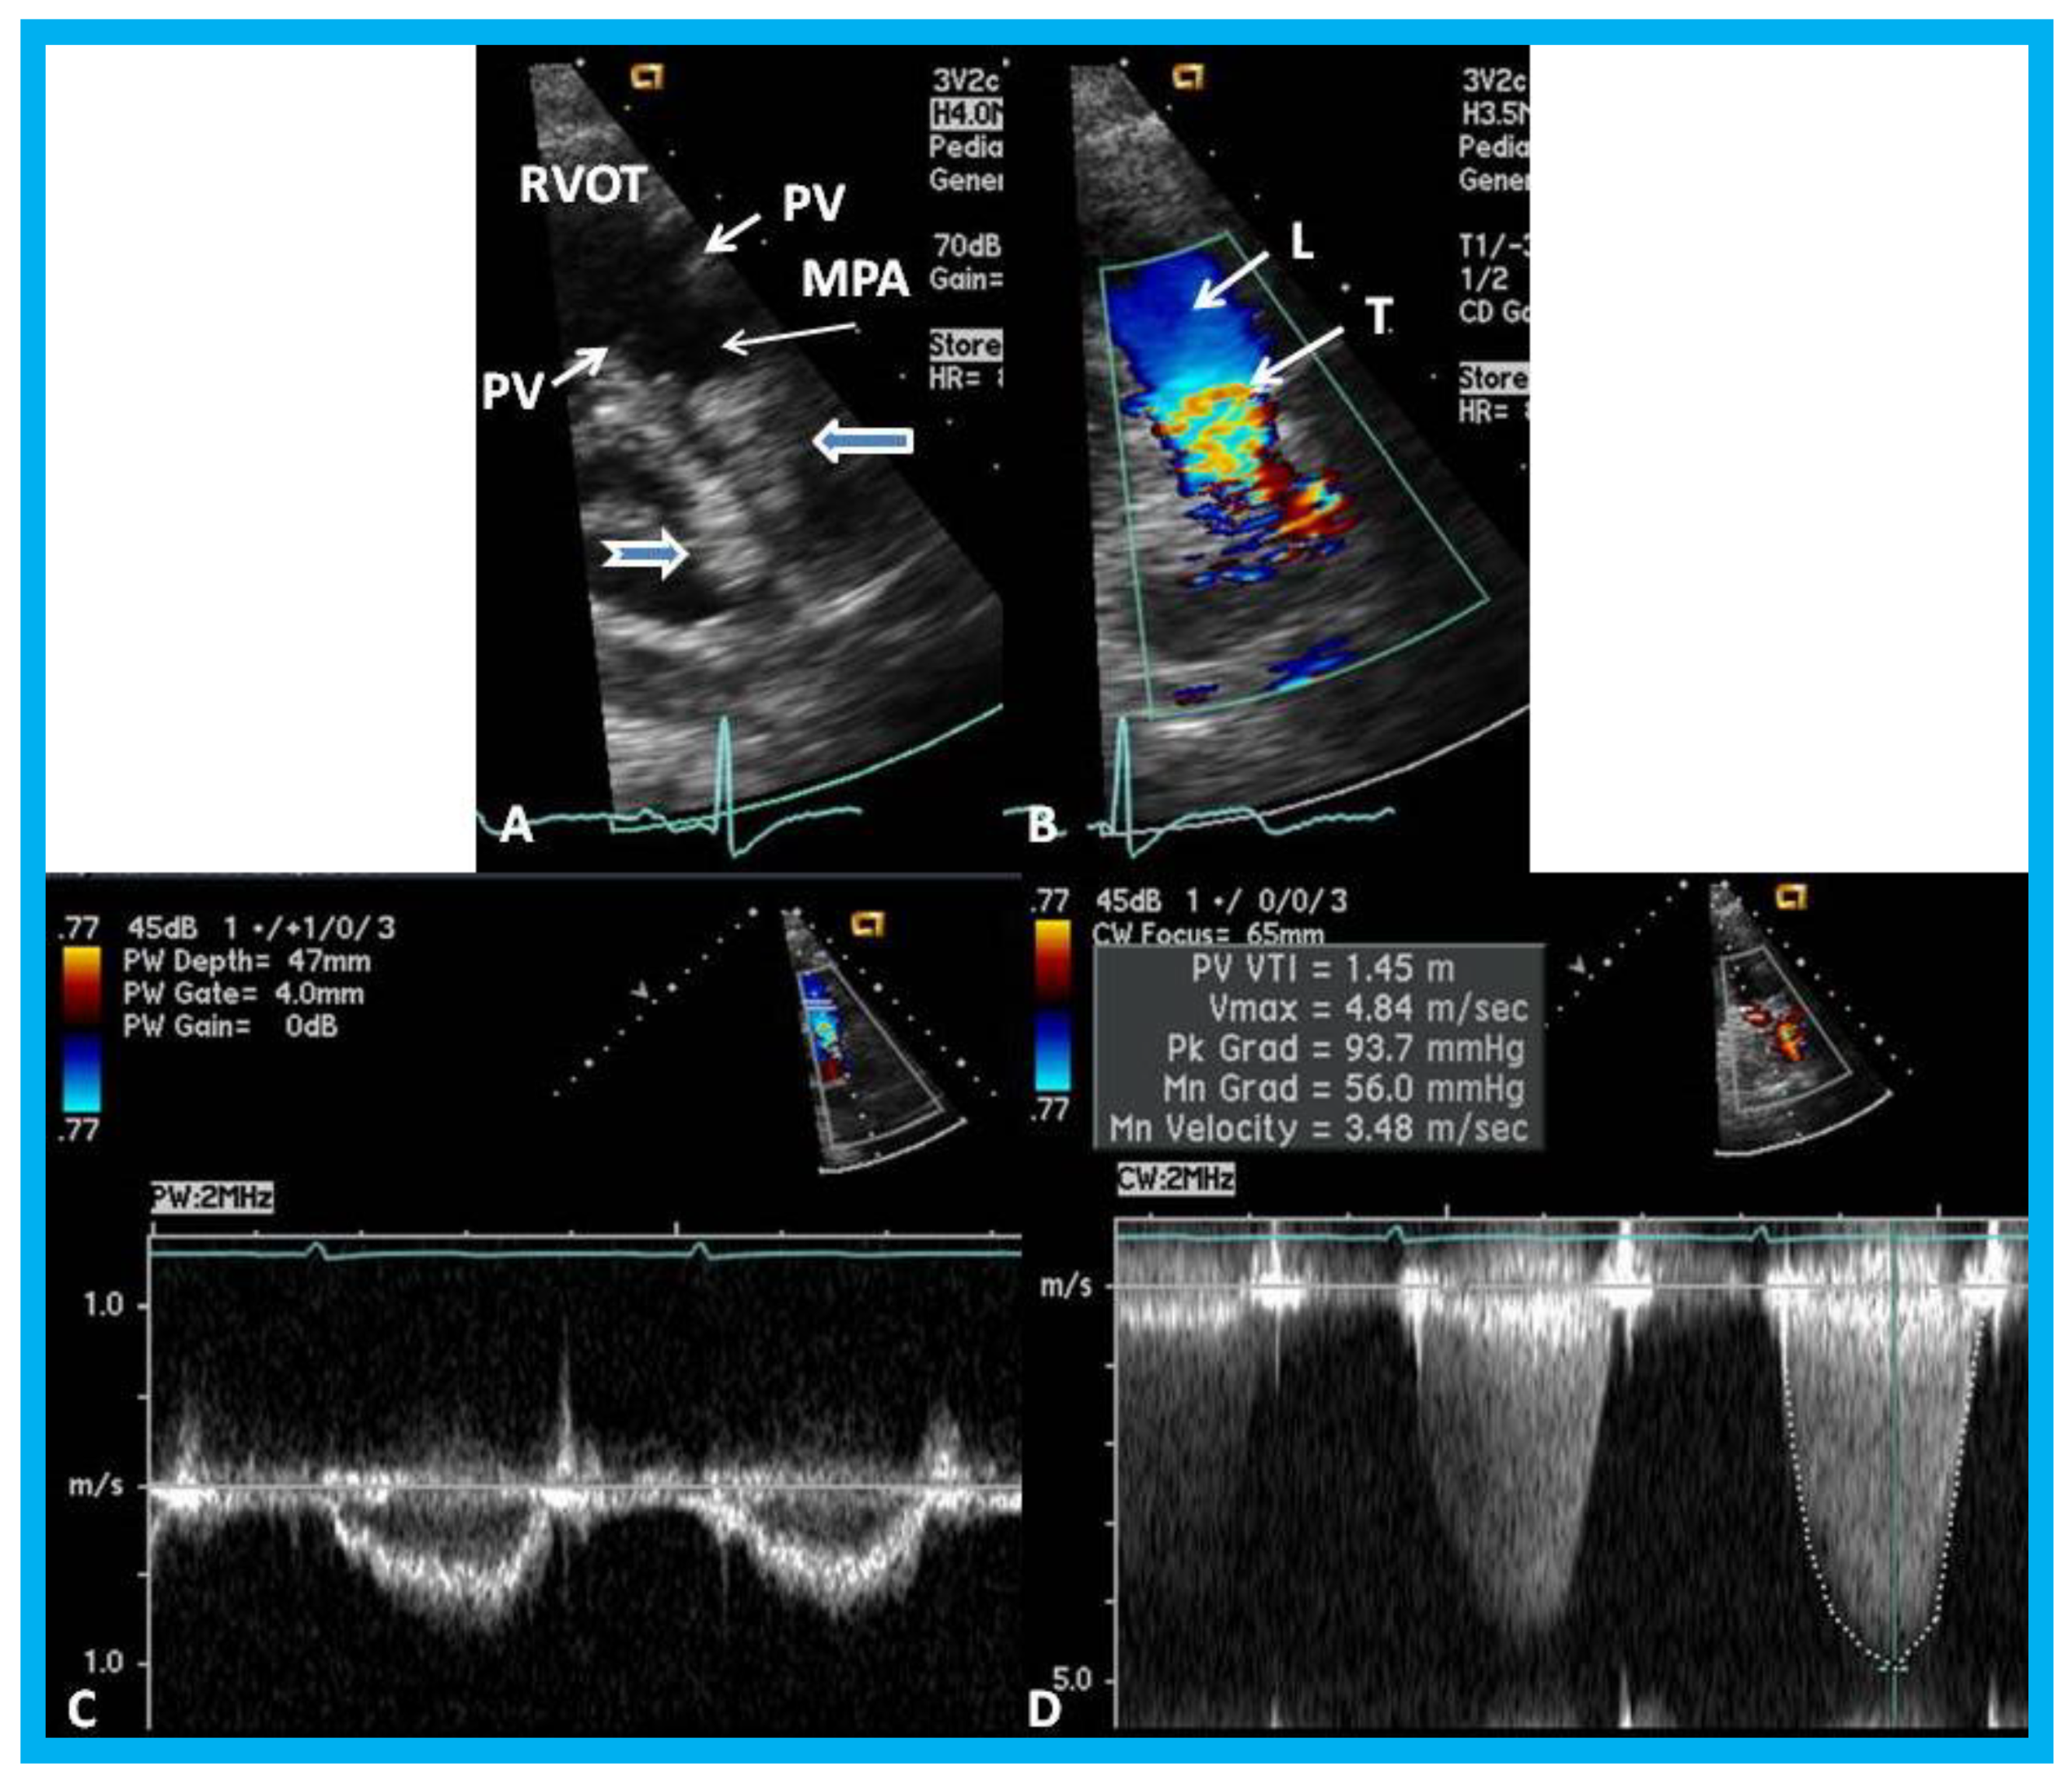

14. Unusual Complication of Supravalvular Pulmonary Artery Stenosis after a Nuss Procedure

An eleven-year-old female patient had a Nuss procedure for treatment of pectus excavatum [30]. A cardiac murmur was heard shortly before the planned Nuss bar removal at the age of thirteen years. Echocardiographic evaluation revealed external compression (Figure 21), causing supravalvar pulmonary stenosis [31]. Removal of the Nuss bar was performed which documented improvement on echo-Doppler studies (Figure 22). Usefulness of echo studies in evaluation of such issues was emphasized.

Figure 21. (A) Selected video frame from a parasternal short axis view showing echo dense structures (thick blue arrows) within and outside the main pulmonary artery (MPA): Pulmonary valve (PV) leaflets (small arrows) are shown and appear normal. The right ventricular outflow tract (RVOT) and proximal MPA are free of any echo-dense structures. (B) Color-Doppler mapping of the same structures as in panel A shows normal laminar (L) flow in the RVOT and proximal MPA and turbulent (T) flow starting in the proximal MPA, indicating obstruction. (C) Pulse Doppler sampling from the proximal MPA, which shows normal flow velocity. (D) Continuous wave Doppler sampling demonstrating high velocity flow across the MPA with a calculated peak instantaneous gradient of 93.7 mmHg and a mean gradient of 56 mmHg, indicating severe obstruction. Reproduced from Mazur L., et al. [31].